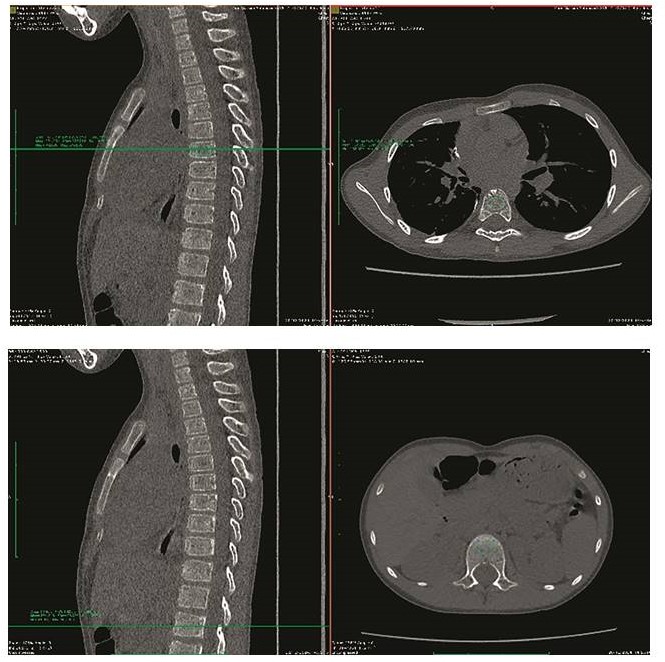

Для уточнения состояния костной системы пациенту был выполнен ряд обследований. По данным проведенной остеоденситометрии поясничного отдела позвоночника от 17.07.2025 снижения минеральной плотности костной ткани не выявлено (рисунок 1).

Рисунок 1

Остеоденситометрия поясничного отдела позвоночника (L1–L4), z-критерий = 0,0 SD (BMD = 0,733 г/см2): нормальная минеральная костная плотность с учетом возраста

Figure 1

Densitometry of the lumbar spine (L1–L4), z-score = 0.0 SD (BMD = 0.733 g/cm2): normal mineral bone density appropriate for the patient’s age